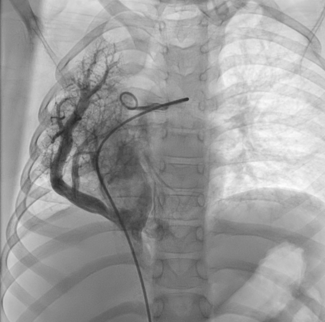

Gayathri Bhuvaneswaran Kartha, DM; Shruti Irene Varghese, DM; Anoop George Alex, DM; Oommen K. George, DM

An 8-year-old girl presented with persistent pneumonia of a 1-month duration and right lower zone opacity on chest X-ray. Computed tomography of her thorax revealed right lung hypoplasia with partial anomalous pulmonary venous drainage of the...